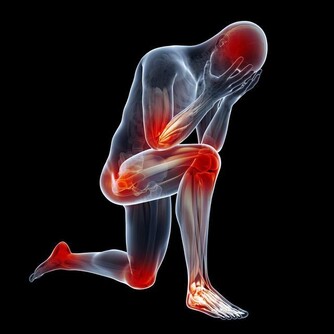

卵巢癌早期可能會出現腹部的持續腫脹,有壓迫感和疼痛、腸胃不適、進食困難等,或者極易有飽食感、尿頻或尿急等。

卵巢癌的早期症狀,腹脹、背痛、脹痛或不適、腹圍增大、便秘、疲乏、尿頻或尿急、不能正常進食、原因不明的體重減輕。

(3) 壓迫症狀,當腫瘤向周圍組織浸潤或壓迫神經時,可引起腹痛、腰痛或坐骨神經痛,若壓迫盆腔靜脈,可出現下肢浮腫;巨大的腫瘤可壓迫膀胱,有尿頻、排尿難、尿瀦留;壓迫直腸則大便困難;壓迫胃腸道便有消化道症狀;壓迫膈肌可發生呼吸困難,不能平臥。

(5)疼痛,因癌腫轉移而出現相應的症狀,卵巢惡性腫瘤極少引起疼痛,如發生腫瘤破裂、出血或感染或由於浸潤壓迫鄰近臟器可引起腹痛、腰痛。